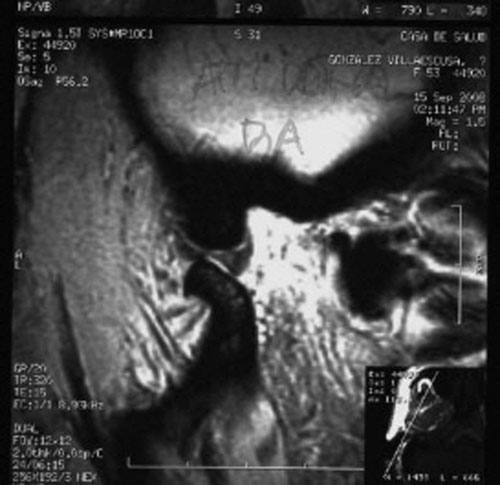

RMN de ATMs (17-09-2008): Dentro de la normalidad.

– ATMs dentro de la normalidad.

PRUEBAS DIAGNOSTICAS COMPLEMENTARIAS: